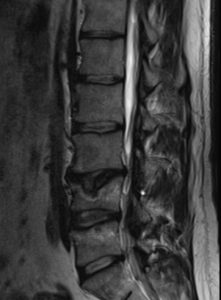

Se aprecia en RM migración de contenido discal en la esponjosa (hernia de Schmorl postraumático) que podría causar los síntomas.